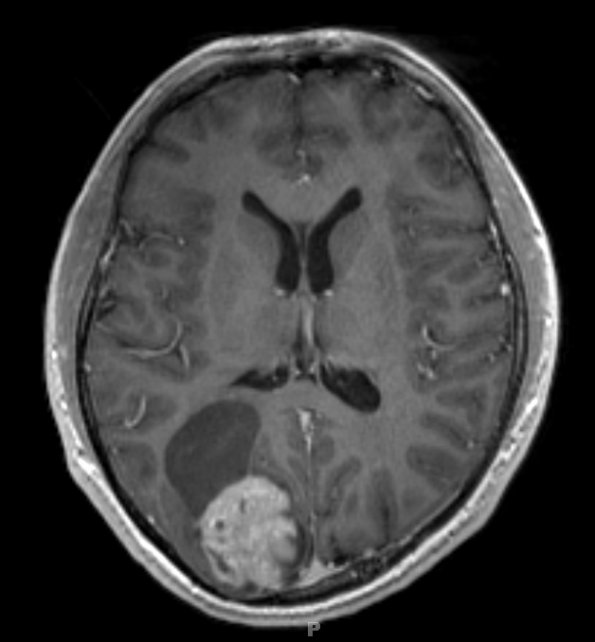

Case 19 History ---- The patient is a 17-year-old boy who experienced new onset seizures with a visual aura and subsequently experienced generalized tonic/clonic seizures. MRI showed a ~4 cm solid and cystic, contrast-enhancing, mildly diffusion-restricting, spherical mass in the right parietal occipital lobe, accompanied by a ~6-7 cm anterosuperior cystic component, and some skull remodeling. Operative procedure: Right occipital craniotomy for gross total resection. ---- 19A1 This T1 weighted scan with contrast administered shows a cystic neoplasm with an enhancing mural nodule.